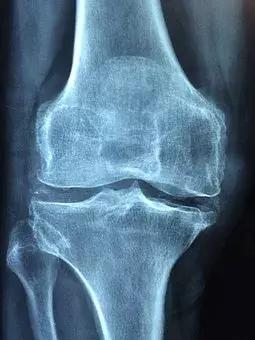

左侧:健康的膝关节,右侧:存在软骨磨损、骨刺、关节退行性变的膝关节